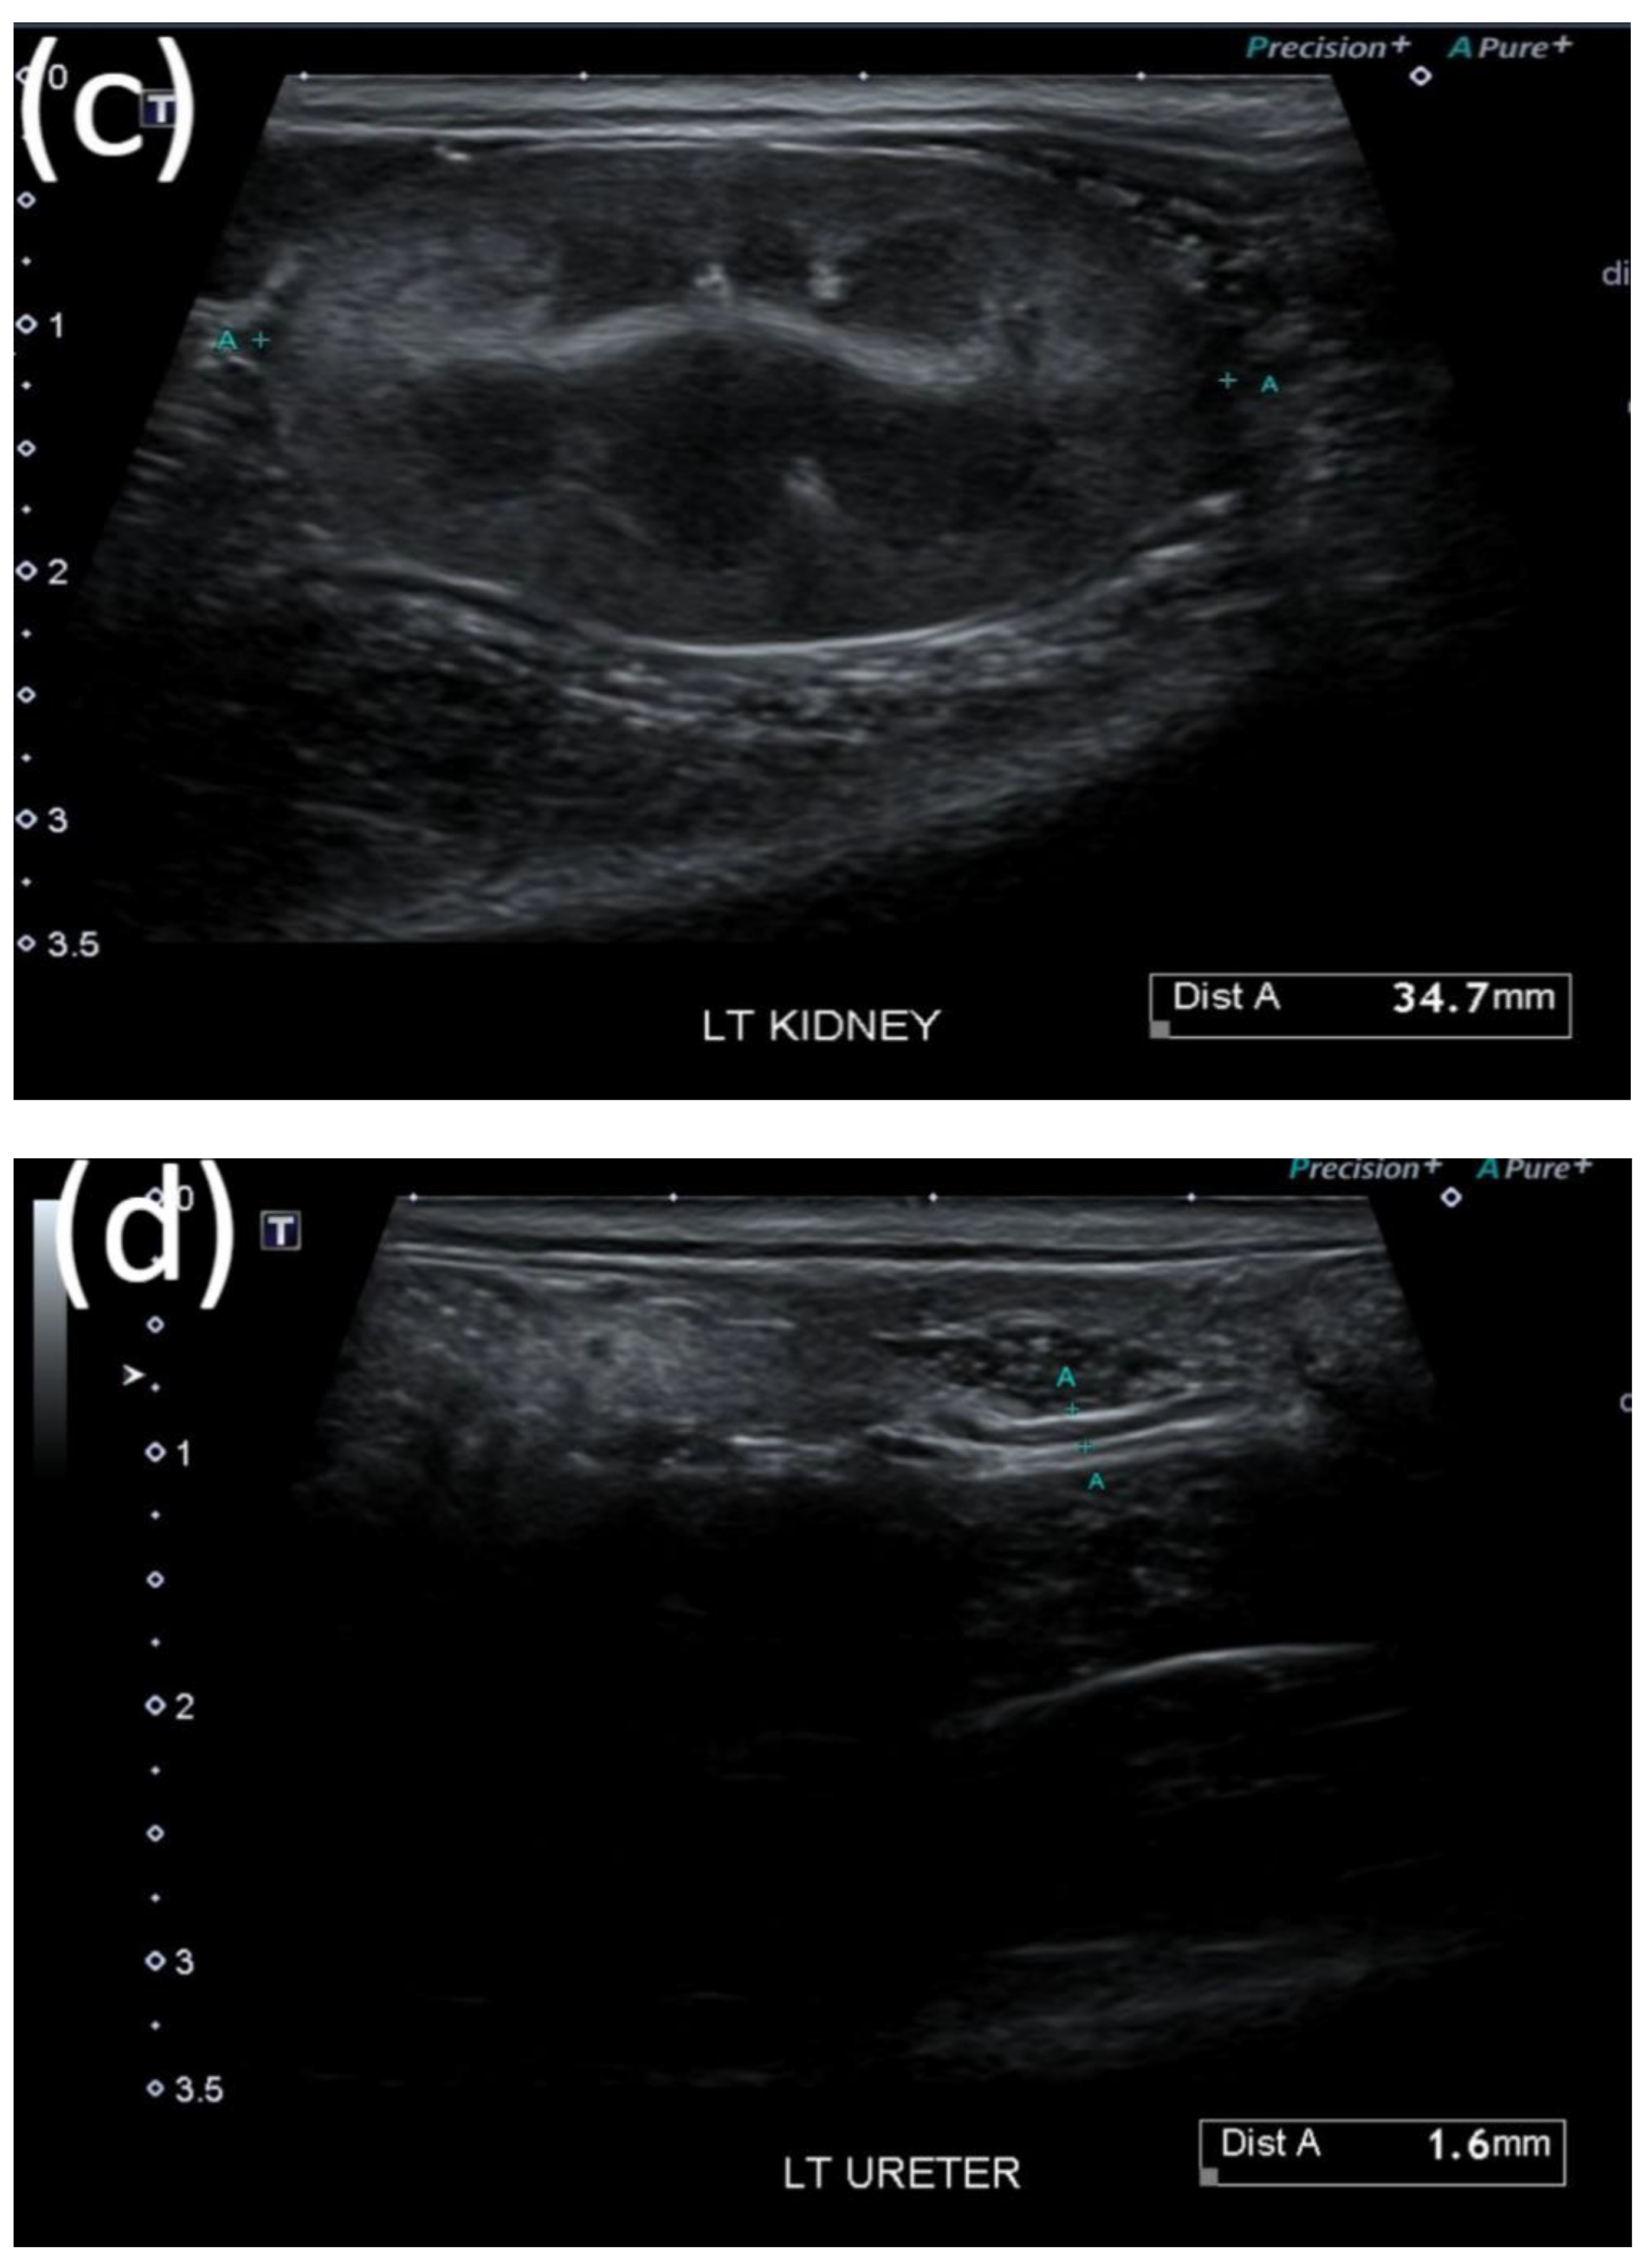

2.3. Evaluation of Treatment Response

3.2. Diagnostic Tests